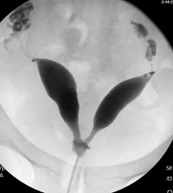

Septation of the uterus & cervix, & unicolpus

Uterus Didelphys

Uterus Didelphys with septated Vagina